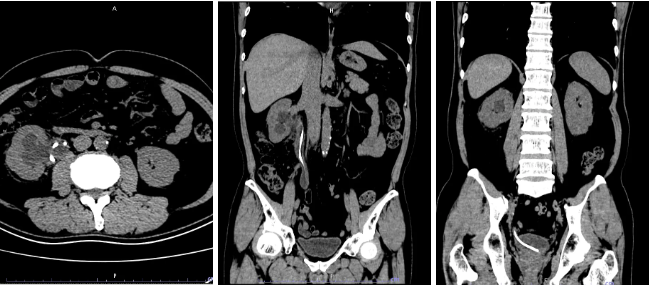

今年 4 月,患者胡先生(50 岁)在该院接受泌尿系微创手术后,置入了一根输尿管支架管,医嘱要求 3 个月后复诊拔除。然而,因个人原因,胡先生直到 8 个月后才因腰部持续不适到医院就诊。影像检查显示:支架管全程(上段、中段、下段)均被大小不一的结石包裹,管壁与结石紧密粘连,拔除难度较高。